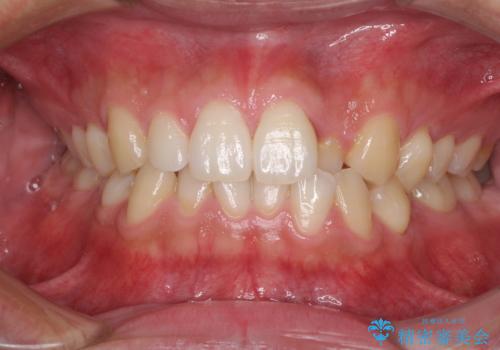

[ 前歯のねじれ・がたつき ] マウスピース矯正

![[ 前歯のねじれ・がたつき ] マウスピース矯正の症例 治療前](https://seimitsushinbi.jp/wp/wp-content/uploads/2024/02/4007c6479f6bce11863dcdd32ed5e39b-500x350.jpg?v=1708502552)

![[ 前歯のねじれ・がたつき ] マウスピース矯正の症例 治療後](https://seimitsushinbi.jp/wp/wp-content/uploads/2024/02/e7a01485e4f4dd0da04705fde4cc34cc-500x350.jpg?v=1708502585)

インビザライン モニター治療 前歯のねじれをまっすぐに